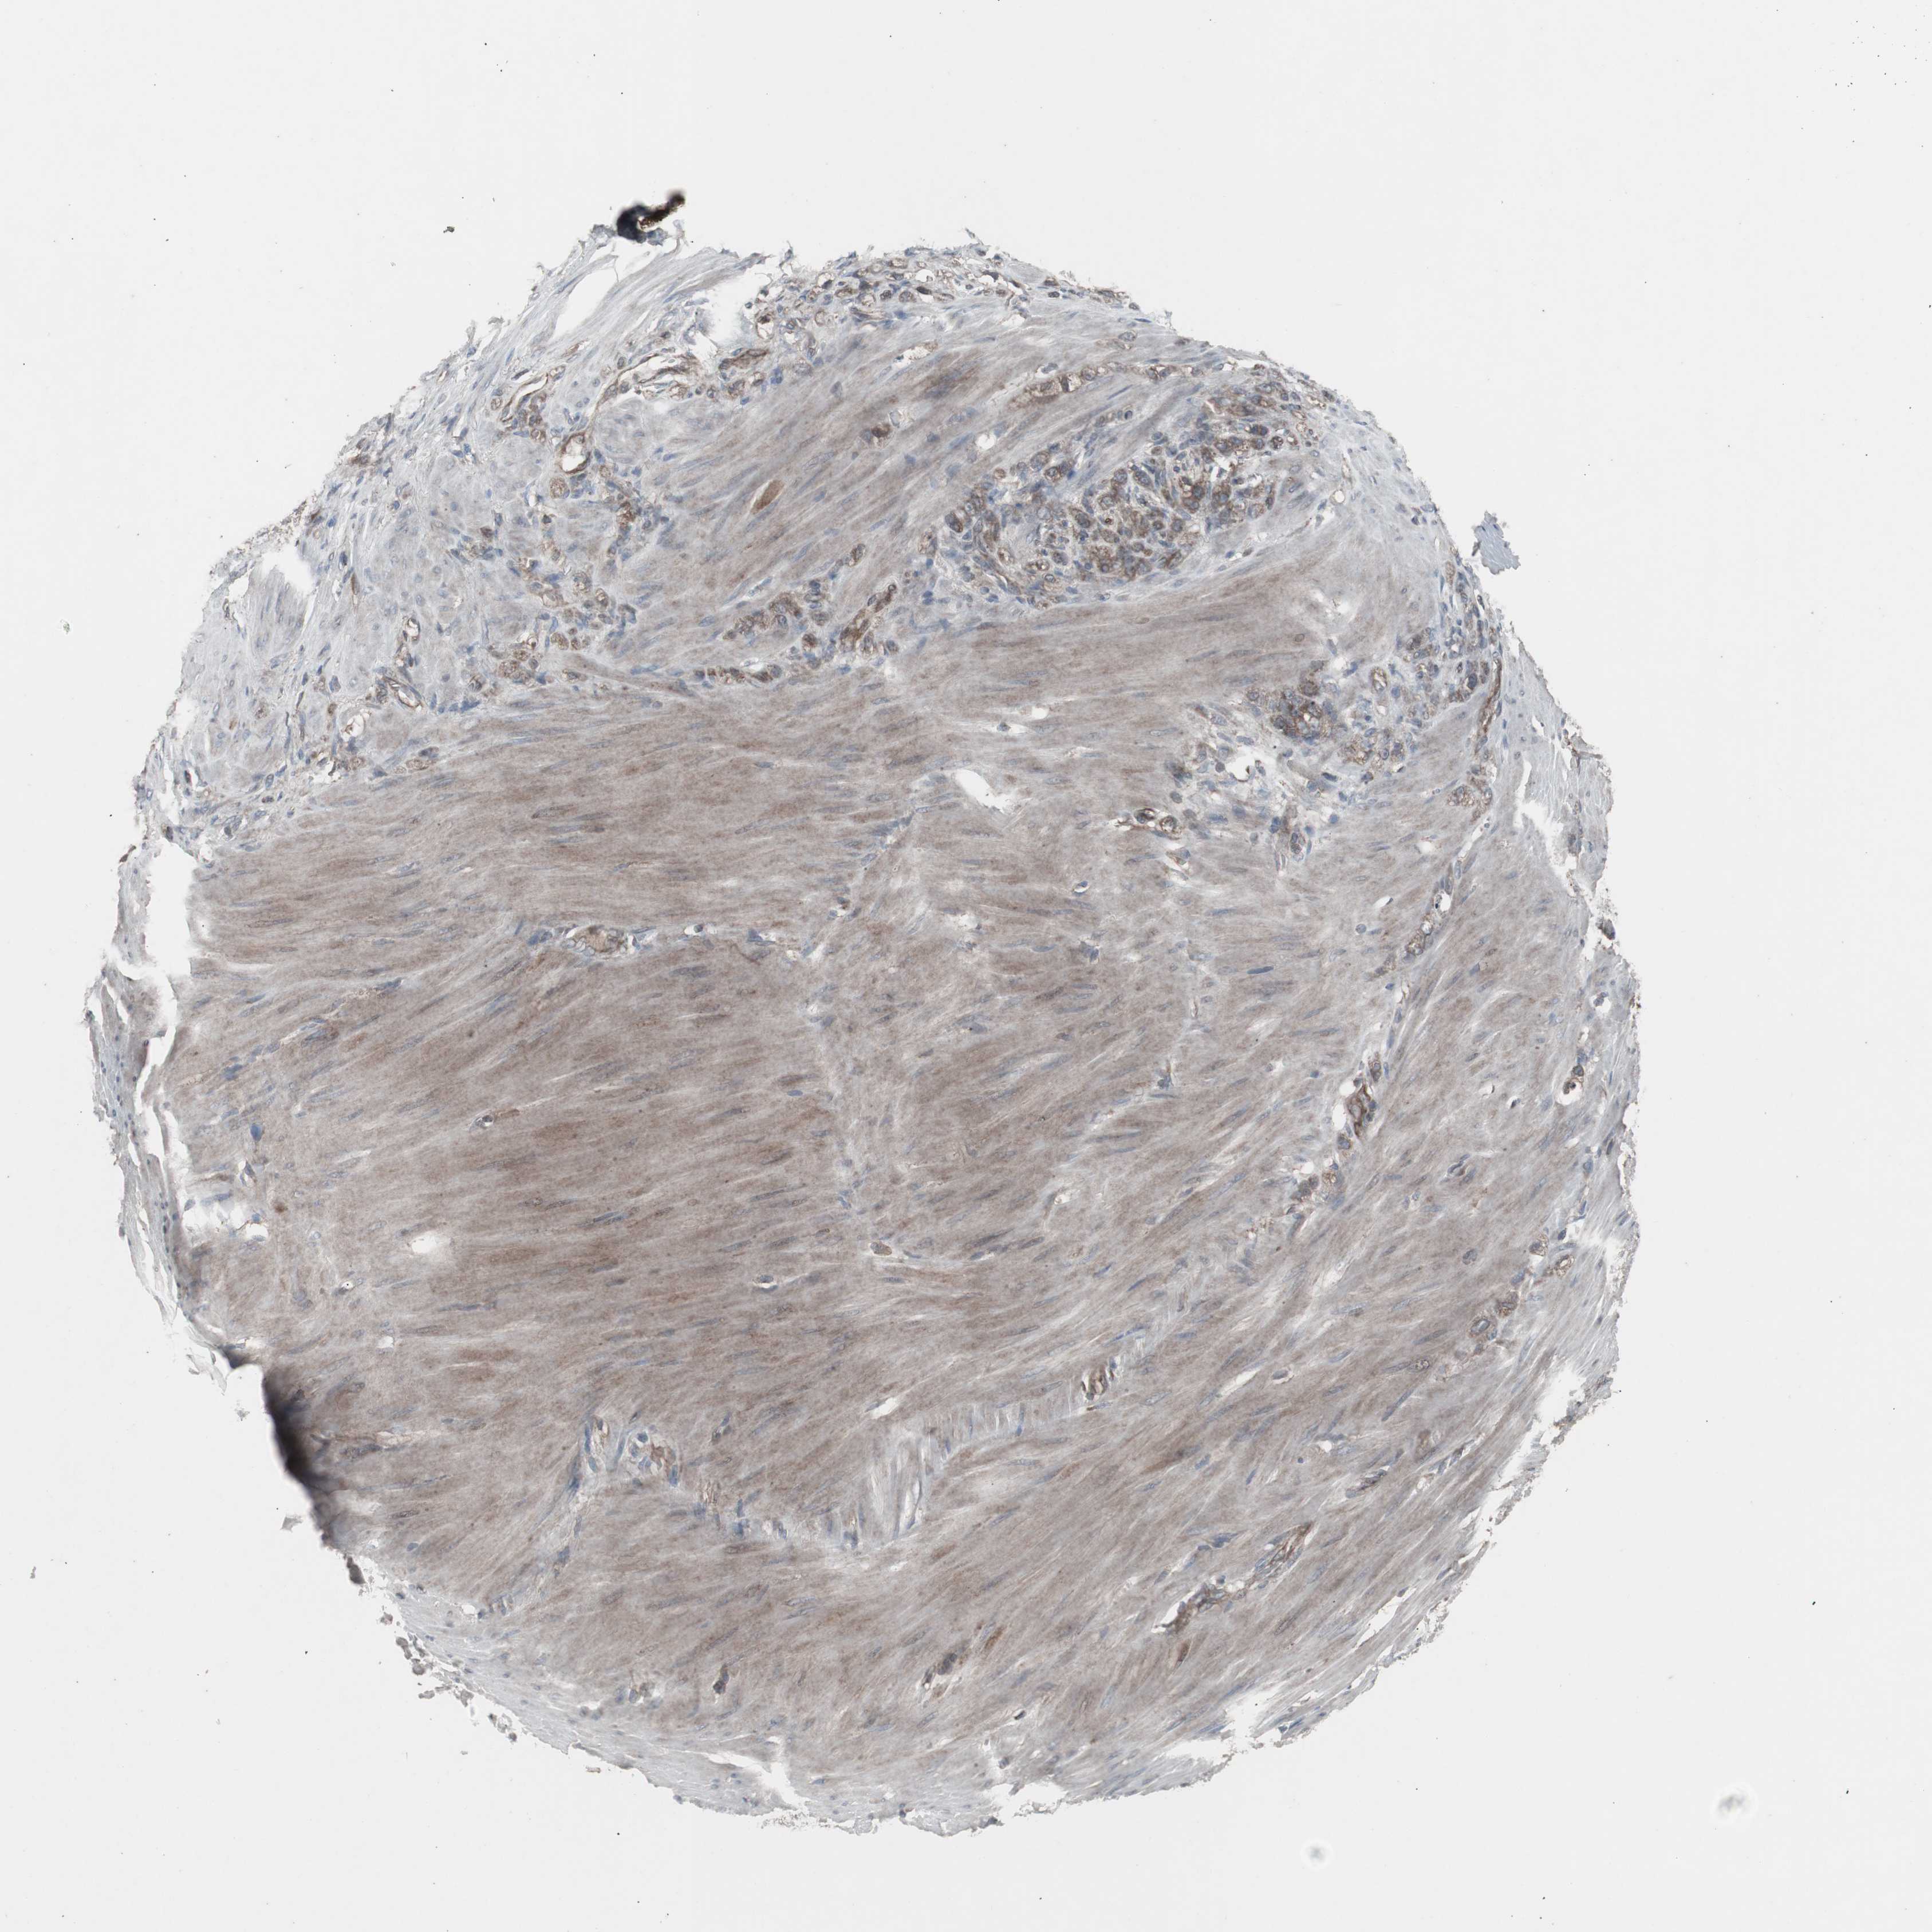

STOMACH CANCER - Protein expressioni

A mouse-over function shows sample information and annotation data. Click on an image to view it in a full screen mode. Samples can be filtered based on level of antibody staining by selecting one or several of the following categories: high, medium, low and not detected. The assay and annotation is described here.

Note that samples used for immunohistochemistry by the Human Protein Atlas do not correspond to samples in the TCGA dataset.

Antibody stainingi

Antibody staining in the annotated cell types in the current human tissue is reported as not detected, low, medium, or high, based on conventional immunohistochemistry profiling in selected tissues. This score is based on the combination of the staining intensity and fraction of stained cells.

Each image is clickable and will lead to virtual microscopy that enables deeper exploration of all samples and also displays staining intensity scores, fraction scores and subcellular localization as well as patient and tissue information for each sample.

Antibody HPA007264

Staining

High

Medium

Low

Not detected

Intensity

Strong

Moderate

Weak

Negative

Quantity

>75%

75%-25%

<25%

None

Location

Nuclear

Cytoplasmic/membranous

Cytoplasmic/membranous,nuclear

Adenocarcinoma, NOS

Adenocarcinoma, High grade